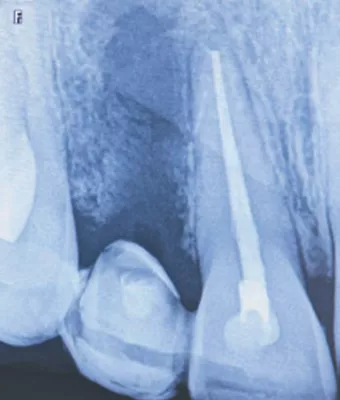

FIG 1:

X-Ray of 36 year old malepatient who had undergone repeated root canal treatment, two apicoectomy procedures and a poorly done stabilisation over the past few years at some other clinic. But there was a fistula with purulent discharge and accompanying pain and inflammation in the region warranting tooth extraction.